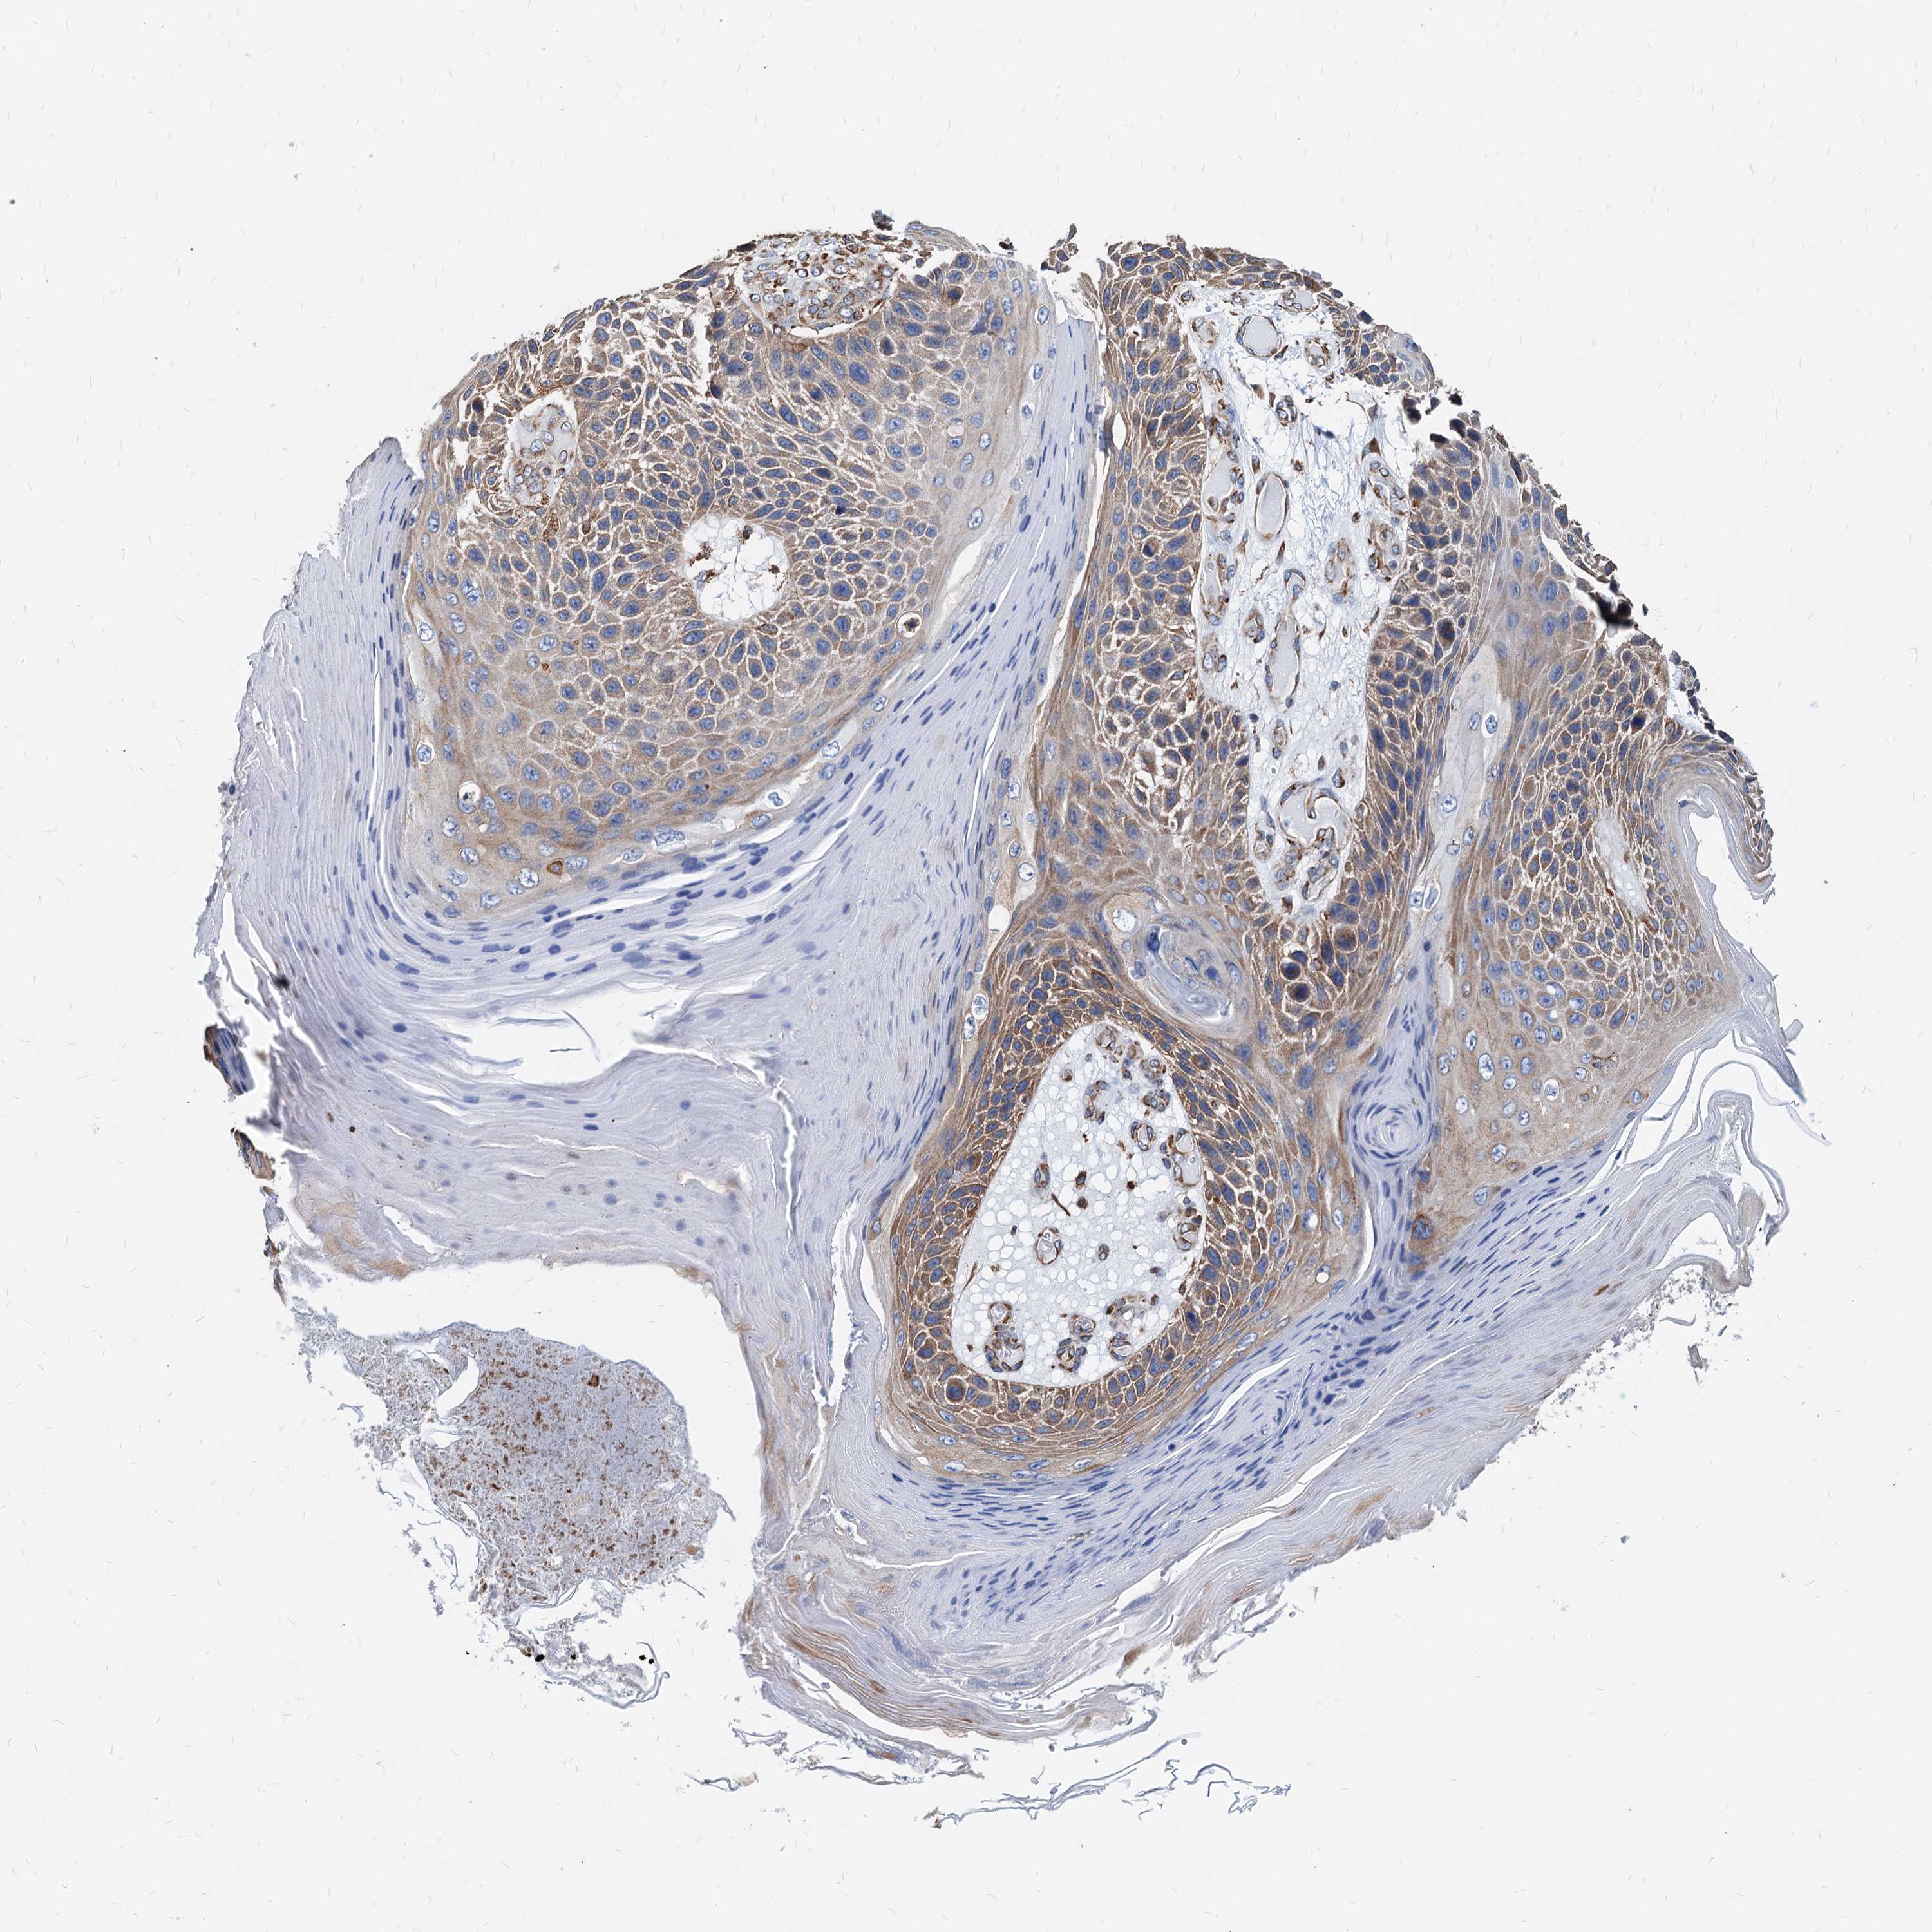

Basal cell and squamous cell cancer

SKIN CANCER - Protein expressioni

A mouse-over function shows sample information and annotation data. Click on an image to view it in a full screen mode. Samples can be filtered based on level of antibody staining by selecting one or several of the following categories: high, medium, low and not detected. The assay and annotation is described here.

Each image is clickable and will lead to virtual microscopy that enables deeper exploration of all samples and also displays staining intensity scores, fraction scores and subcellular localization as well as patient and tissue information for each sample.

Antibody HPA038845

Antibody HPA038846

Antibody CAB005221

Basal cell carcinoma